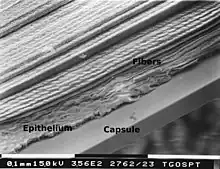

The lens capsule is a transparent membrane that surrounds the entire lens. The capsule is thinnest at the posterior pole with approximate thickness of 3.5μm. Average thickness at the equator is 7μm.[5][9] Anterior pole thickness increases with age from 11-15μm. The thickest portion is the annular region surrounding the anterior pole. This will also increases with age (from 13.5-16μm).[10] The ligaments suspending the lens form attachments in the equatorial area and more so just to the front and back of the equator.[11] There are tens of thousands of these ligaments in a mouse lens and for the most part they appear to connect directly to the lens capsule.[12]

As the lens grows throughout the life of most vertebrates the capsule is required to grow as well.[13] As shown in the accompanying micrographs and diagrams some ligament anchors have associated cells where they connect to the lens capsule. These cells have periodic cellular processes penetrating the capsule.

The structures in the images are consistent with the laying down of new capsular material required for growth. Even though the capsule is a highly elastic structure,[14] it contains no elastic fibers. Elasticity is because of the thick lamellar arrangement of the collagen fibers.[10]